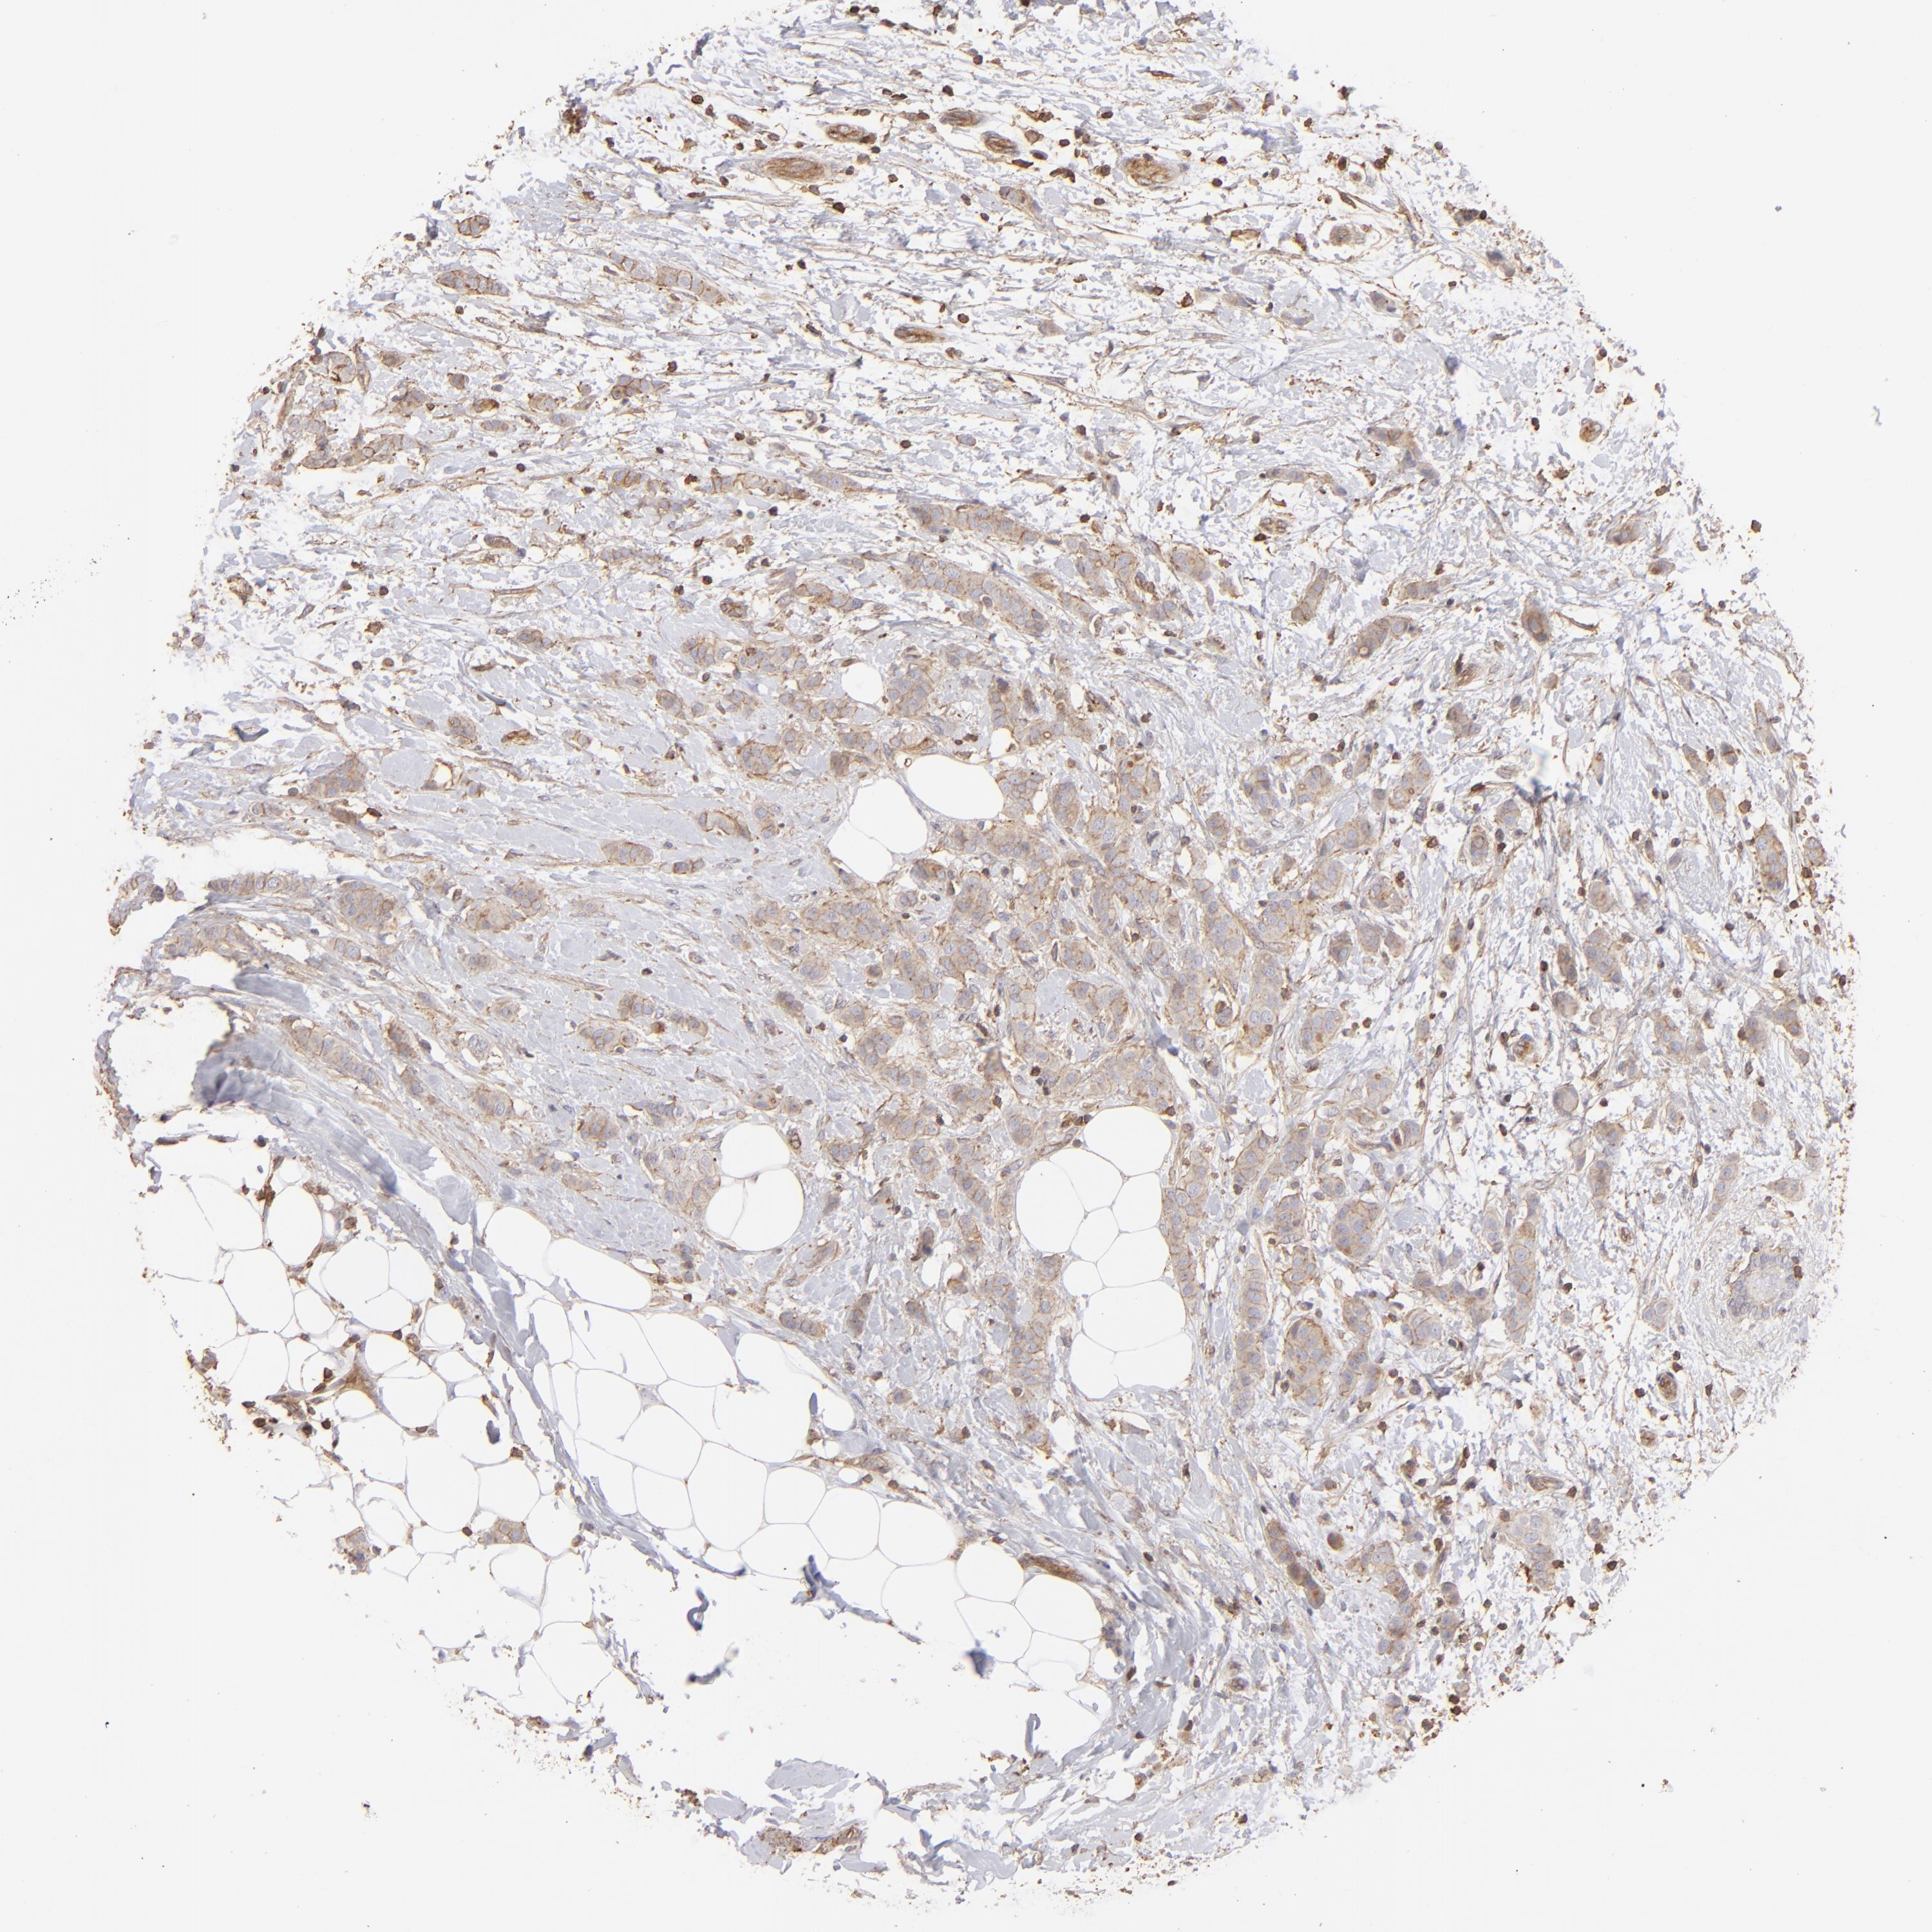

BRCA TCGA BRCA VALIDATION PROTEIN EXPRESSION

Breast cancer

Human cancer

Breast invasive carcinoma